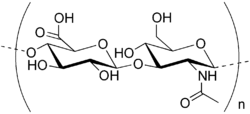

Chondroitin

Like glucosamine, chondroitin is another major component of cartilage. Chondroitin can be manufactured synthetically, but is usually extracted from cow and shark cartilage. Chondroitin is in dietary supplements used as an substitutive medicine to treat osteoarthritis and also approved and regulated as a symptomatic slow-acting drug for this disease (SYSADOA) in Europe and some other countries.[19] It is commonly sold together with glucosamine. Chondroitin and glucosamine are used in veterinary medicine,too.[20]

Major side effects of chondroitin are uncommon but contains hair loss and minor gastrointestinal complaints. The effects of chondroitin on nursing or pregnant women have not been studied well. Chondroitin can decrease the blood’s ability to clot, and it is not good to take it with aspirin, antiplatelet, or anticoagulant drugs. As glucosamine and chondroitin are both components of cartilage, they are sometimes combined in one product. Chondroitin products are also sometimes combined with manganese, which may help cartilage production, but is toxic in large doses. The U.S. National Academy of Sciences has set the adult tolerable upper limit for manganese at 11 mg/day; patients should be advised not to overdose that level[21][22].